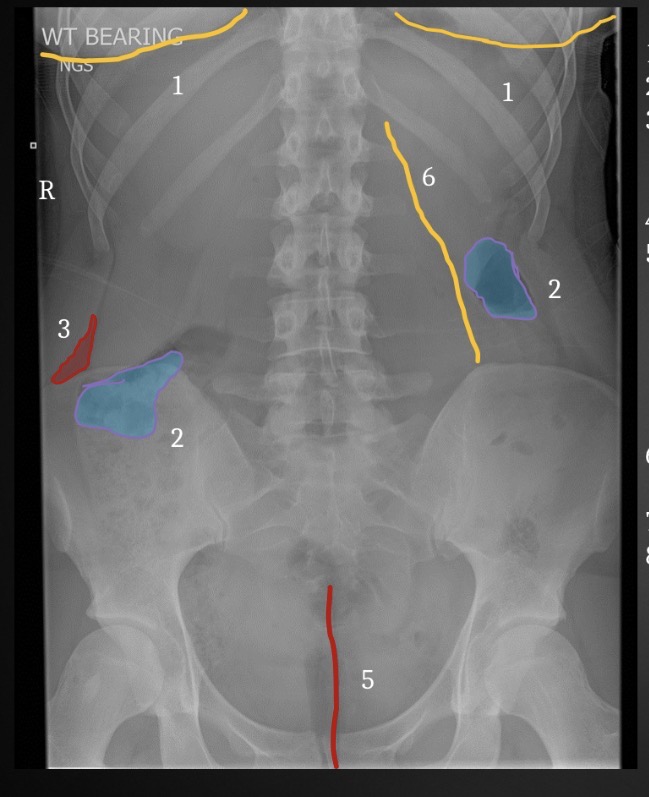

1

Inferior Margin of right 1th rib

2

Spinous process of T12

3

Left pedicle of L2

4

Left transverse process of L3

5

Right facet joint space L2-3

6

L4 spinous process

7

Inferior margin of right lamina L5

8

Right sacral ala

9

Superior margin right 1st anteror sacral foramen

10

Left margin of sacrum

11

Left iliac crest

12

Left posterior iliac spine

13

Superior margin left acetabulum

14

Gonadal shielding

15

Gas in colon

16

Inferior margin of liver